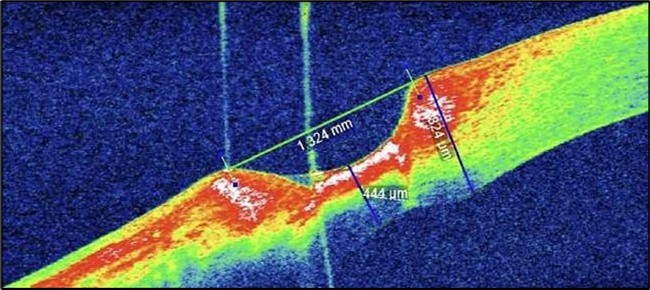

On the current presentation, Snellen VA was 6/6 in the right eye and 6/9 in the left eye, with normal IOP. The left eye demonstrated mild upper lid edema and intense nasal ciliary injection. Slit-lamp evaluation revealed a crescentic area of stromal corneal melting between 7 and 10 o’clock nasally, with overhanging edges and a fluorescein-positive base. No corneal infiltrates were present, and the surrounding stroma remained clear. The anterior chamber was deep and quiet, lens was transparent, pupil was round and reactive & normal posterior segment. Anterior segment optical coherence tomography (AS-OCT) confirmed a localized ulcer, measuring 1324 µm in horizontal width and extending to a depth of 380 μm, compared with an adjacent healthy corneal thickness of 824 µm, corresponding to approximately 46.1% stromal thinning (Figure 1a, Figure 1b, Figure 1c)

Serial anterior segment OCT was employed throughout treatment to monitor corneal changes and response to interventions. Figure 7a, Figure 7b, Figure 7c, Figure 7d illustrate the ulcer’s progression: initial severity, minimal early response to medical therapy, post-operative healing after conjunctival resection, and sustained recovery at six-month follow-up.

Figure 7a.(At presentation): AS-OCT reveals a crescent-shaped peripheral corneal ulcer with marked stromal thinning of 380 µm in depth and complete loss of the overlying epithelium. The ulcer spans 1324 µm in width. The ulcer base appears concave with hyperreflective stromal margins, and a distinct overhanging edge is visible at the inner margin.